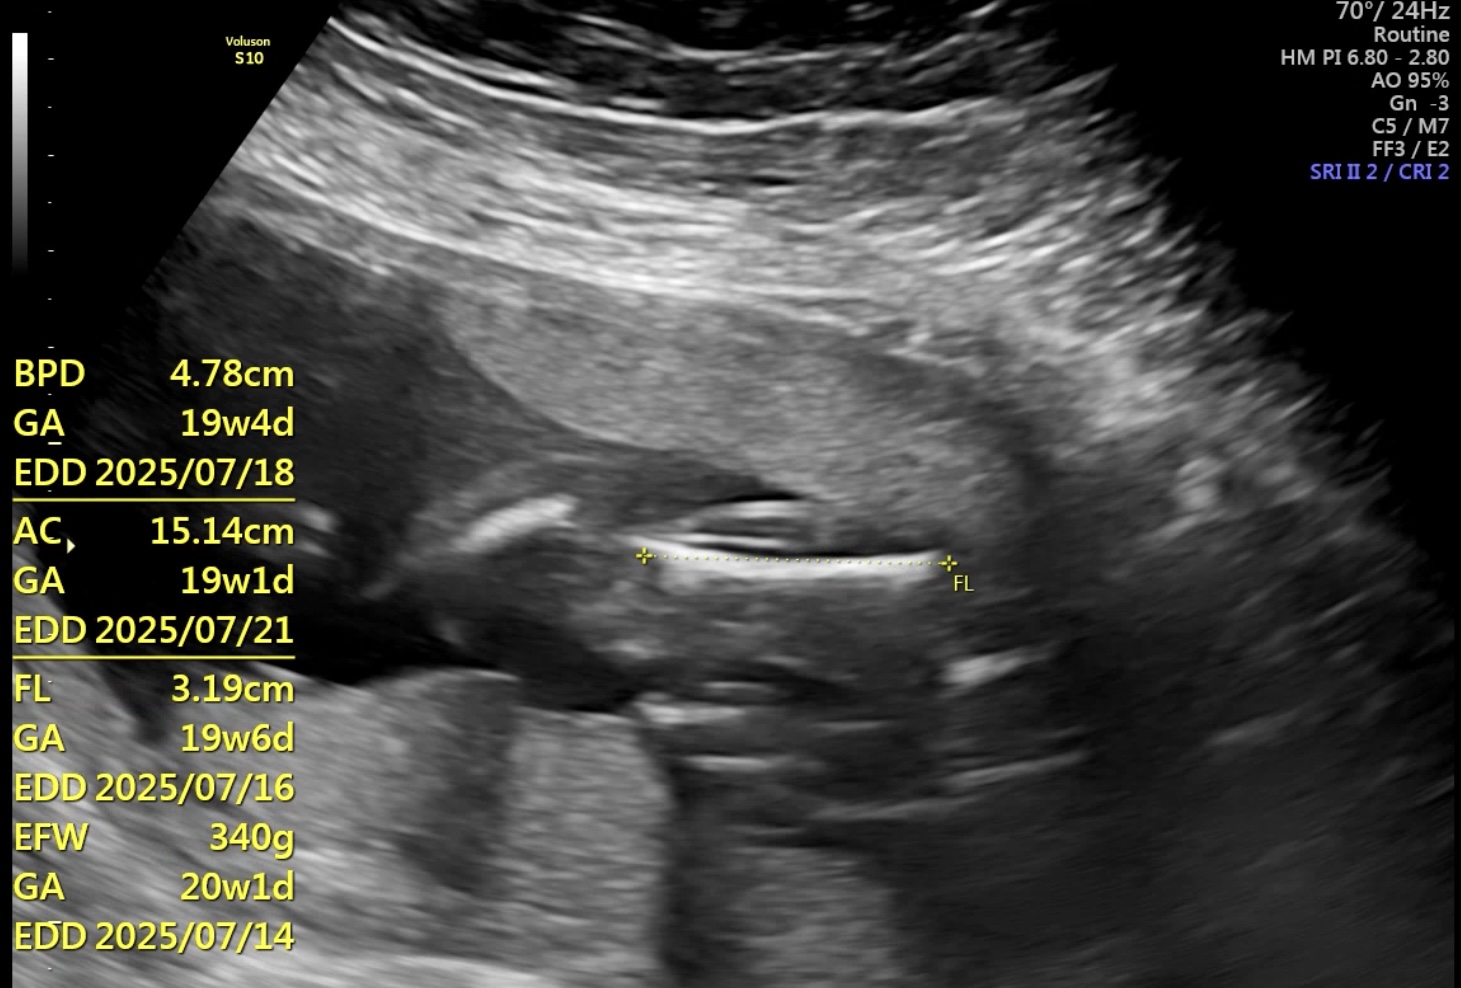

산부인과 정기진료

19주 2일차

정기 진료에서는 항상 태아 무게,

심장 박동수, 양수량을 체크한다.

초음파 검사에서는

평균에 맞게 성장하고 있다는

설명을 들었으며,

현재 태아 무게는 340g이다.

다음 진료는 정밀 초음파로

예정되어 있으며,

정밀 초음파는 담당 교수가 아닌

처음 진료를 보는 교수가

검사를 진행해 보다 꼼꼼히

확인할 예정이라고 안내받았다.

이는 담당 교수가 나의 초음파 영상에

익숙하기 때문에 새로운 시각에서

진단을 받기 위한 절차라고 한다.